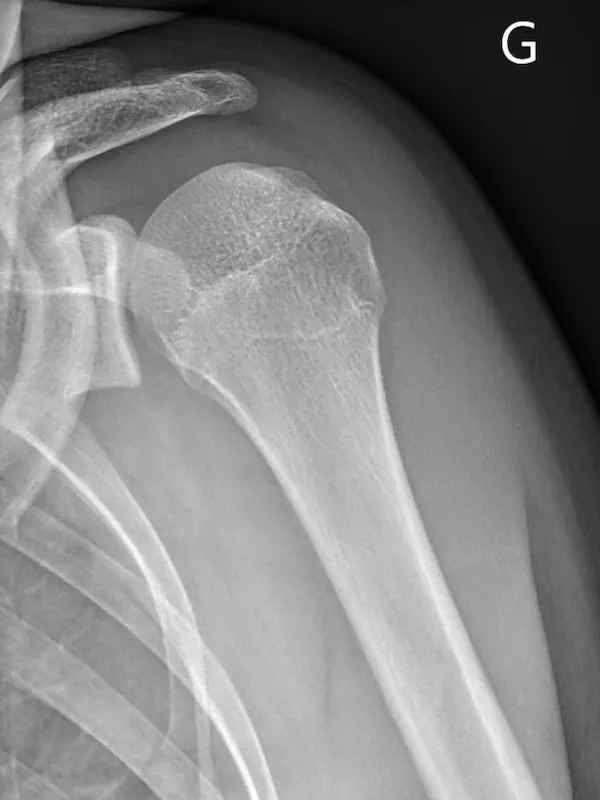

QUELS SONT LES EXAMENS COMPLÉMENTAIRES À RÉALISER ?

Dans un premier temps des radiographies permettent d'avoir une orientation diagnostique en corrélation avec l'examen clinique du chirurgien. Il s’agit du bilan de débrouillage qui sera complété le plus souvent par un arthro-scanner ou une IRM.